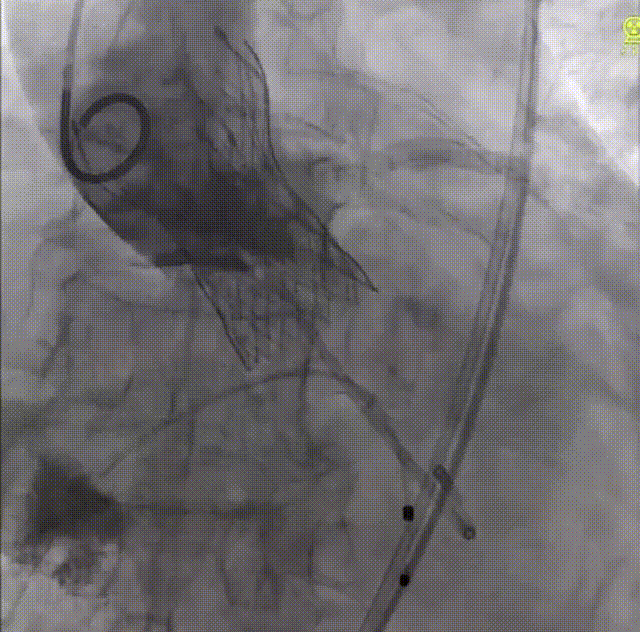

术中经右股静脉穿刺,对主动脉进行血管造影再次确认患者情况,并确定植入支架尺寸。随后,吴文辉教授通过信息采集机器人的高清摄像设备展示了专用于主动脉缩窄的可生长支架CP支架的组装过程,并具体讲解了与之配套的BIB球囊使用方法和效用,该球囊具有双层囊状结构,可均匀扩张CP支架,从而避免形成漏斗形、哑铃形。

CP支架组装过程